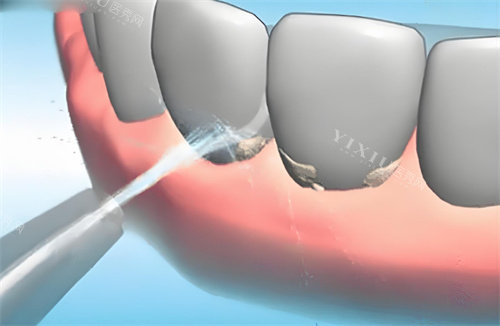

开始洗牙了,张医生的手法特别轻柔,仪器在牙齿上操作的时候,虽然能感觉到有点酸酸麻麻的,但真的没有我想象中那么疼。他还时不时问我感觉怎么样,需不需要休息一下。在洗牙的过程中,张医生还跟我讲了很多日常护牙的小知识,比如刷牙要怎么刷才正确,多久要换一次牙刷,让我受益匪浅。

大概过了半个多小时,洗牙就结束了。洗完之后,我照镜子一看,哇塞,牙齿上的牙结石都没了,牙齿一下子变得白白净净的,感觉自己都能多笑几声了。张医生还叮嘱我,洗牙之后可能牙齿会有点敏感,这几天不要吃太凉太热的东西,还让我定期来检查牙齿。